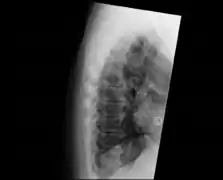

![]() | |

| DISH in an 80 year old female, also with T11 fracture. | |